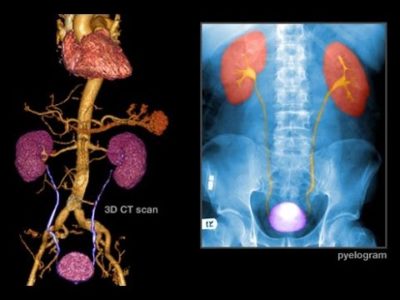

Diagnosing Bladder Cancer 1 – Signs, Symptoms & Tests

This webinar covers risk factors for bladder cancer, signs and symptoms of the disease, and tests used to diagnose bladder cancer such... Learn More

Bladder Cancer: Symptoms, Signs and Diagnostic Tests

. This webinar covers risk factors for bladder cancer, signs and symptoms of the disease, and tests used to diagnose bladder cancer... Learn More